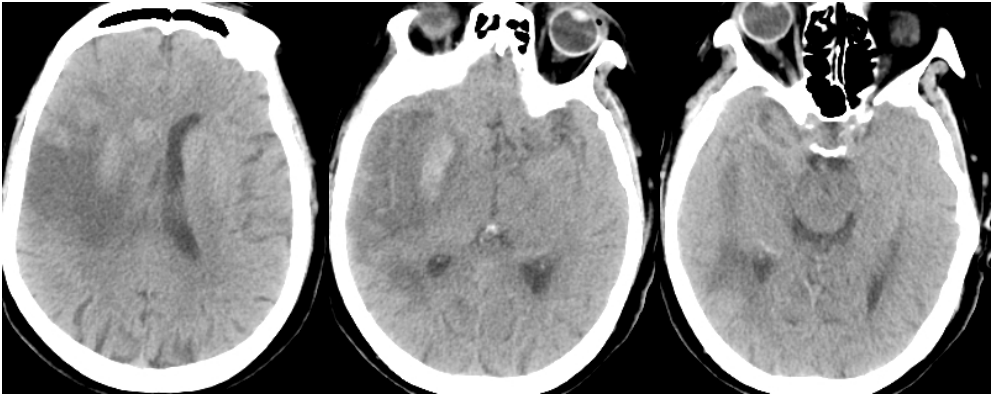

辅助检查

右侧颈内动脉造影显示右侧颈内动脉闭塞。

侧枝代偿差。

选择4.0×20mm支架,采用swim技术取栓2次,取出少量暗红色血栓,颈动脉造影未见血流恢复,单支架取栓无效。

考虑血栓负荷量大,遂采用双支架取栓技术。

梗死合并少量出血,暂不给与抗凝抗血小板药物,给与脱水、营养神经、清除脑自由基、改善循环、补液营养支持以及抗感染等药物治疗。

术后5月复查CTA显示右侧颈内动脉及大脑中血流通畅。